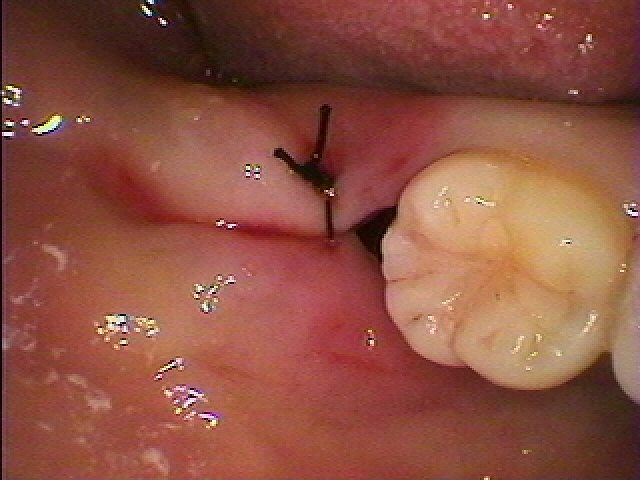

抜歯後、縫合して終了となります

余分な切開を加えていないので出血もありません

1週後にはこのように綺麗に治癒してきています